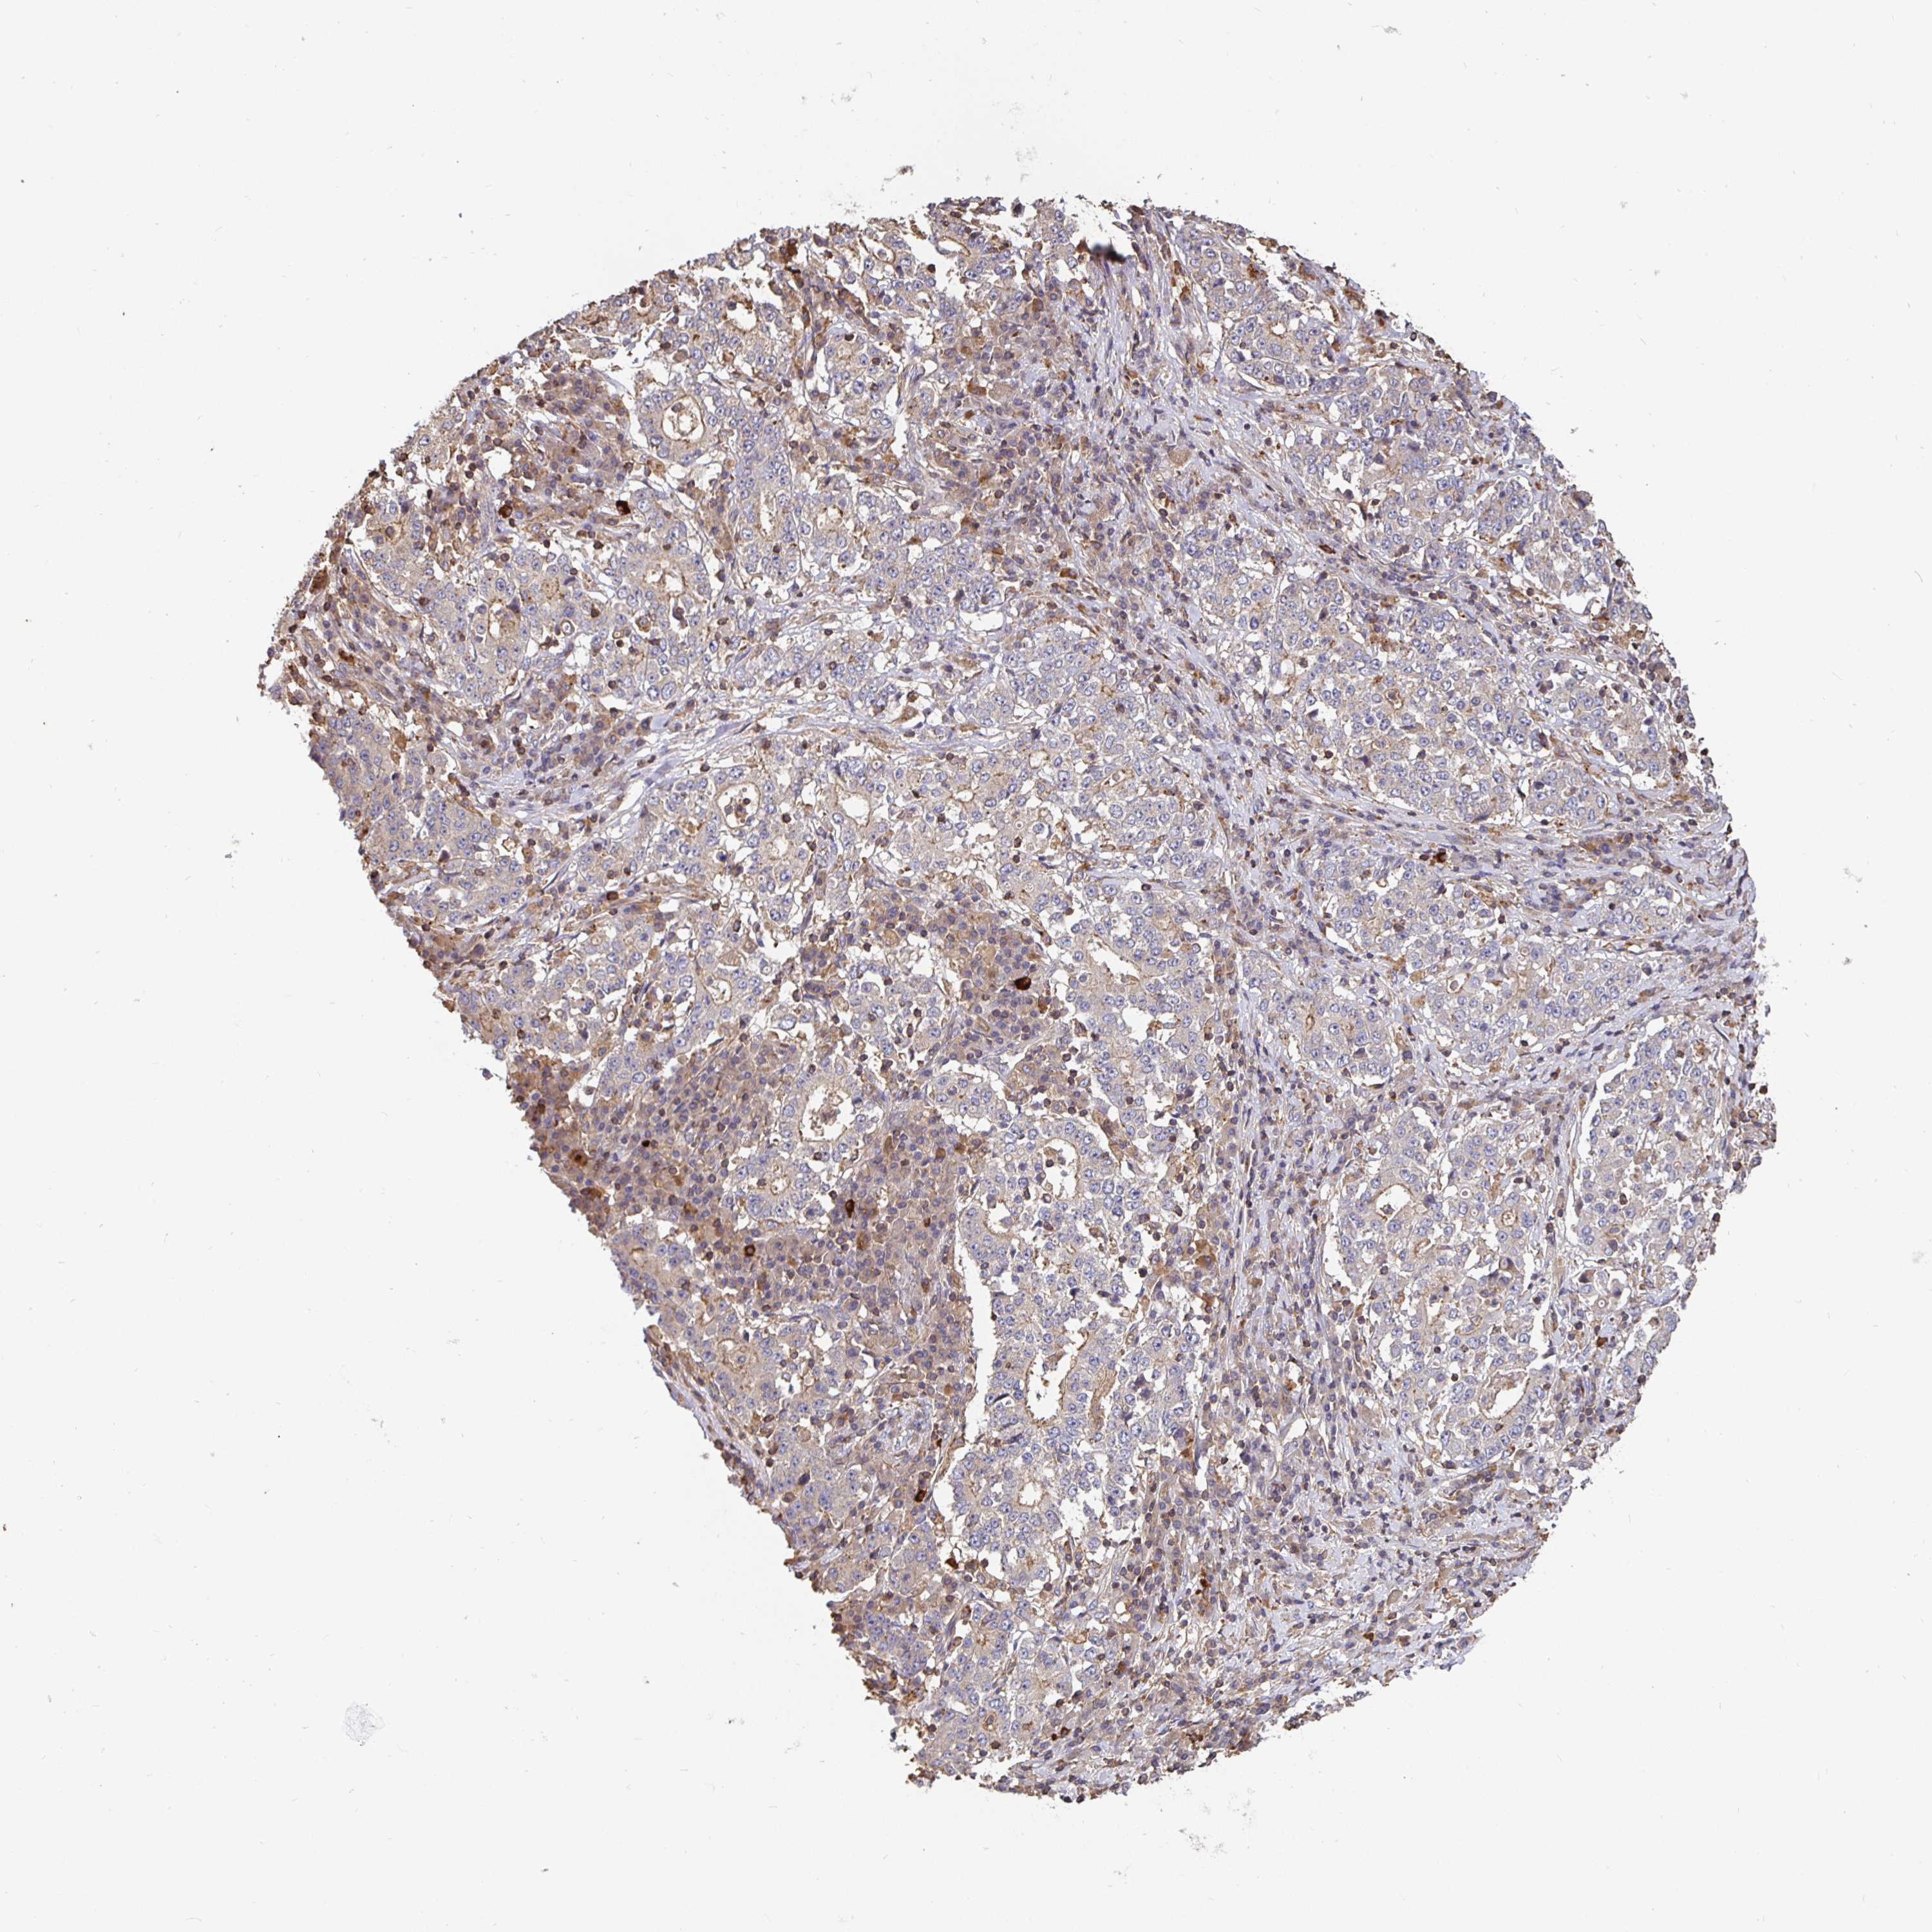

STOMACH CANCER - Protein expressioni

A mouse-over function shows sample information and annotation data. Click on an image to view it in a full screen mode. Samples can be filtered based on level of antibody staining by selecting one or several of the following categories: high, medium, low and not detected. The assay and annotation is described here.

Note that samples used for immunohistochemistry by the Human Protein Atlas do not correspond to samples in the TCGA dataset.

Antibody stainingi

Antibody staining in the annotated cell types in the current human tissue is reported as not detected, low, medium, or high, based on conventional immunohistochemistry profiling in selected tissues. This score is based on the combination of the staining intensity and fraction of stained cells.

Each image is clickable and will lead to virtual microscopy that enables deeper exploration of all samples and also displays staining intensity scores, fraction scores and subcellular localization as well as patient and tissue information for each sample.

Antibody HPA051797

Staining

High

Medium

Low

Not detected

Intensity

Strong

Moderate

Weak

Negative

Quantity

>75%

75%-25%

<25%

None

Location

Nuclear

Cytoplasmic/membranous

Cytoplasmic/membranous,nuclear

Adenocarcinoma, NOS